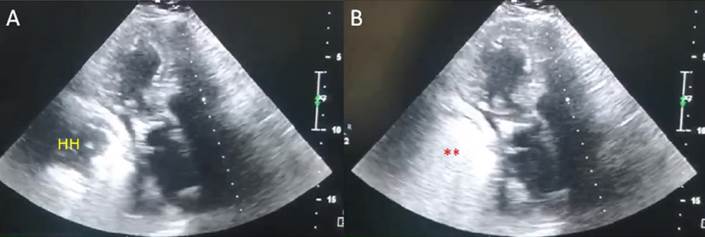

Luego, con este planteo se realiza un nuevo ecocardiograma Doppler con el fin de contar con una técnica de mayor accesibilidad para un eventual seguimiento cardiovascular. En este se constata una regular ventana ultrasónica y se evidencia una masa retroauricular en íntimo contacto con la aurícula izquierda y sobre pared inferolateral del ventrículo izquierdo de difícil caracterización (figura 2A). Contando con la información de la resonancia se completa el estudio ecocardiográfico y se le pide a la paciente que ingiera una bebida carbonatada en decúbito supino (en este caso, agua con gas, a modo de “contraste”). Se visualiza el pasaje de las microburbujas al interior de la masa (en este caso, el estómago), lo que permite confirmar el diagnóstico ecocardiográfico de hernia hiatal (figura 2B). Dados estos hallazgos en los estudios de multimodalidad de imagen cardiovascular, es enviada por su médico tratante a valoración por equipo de gastroenterología y cirugía para definir directivas del tratamiento a seguir.